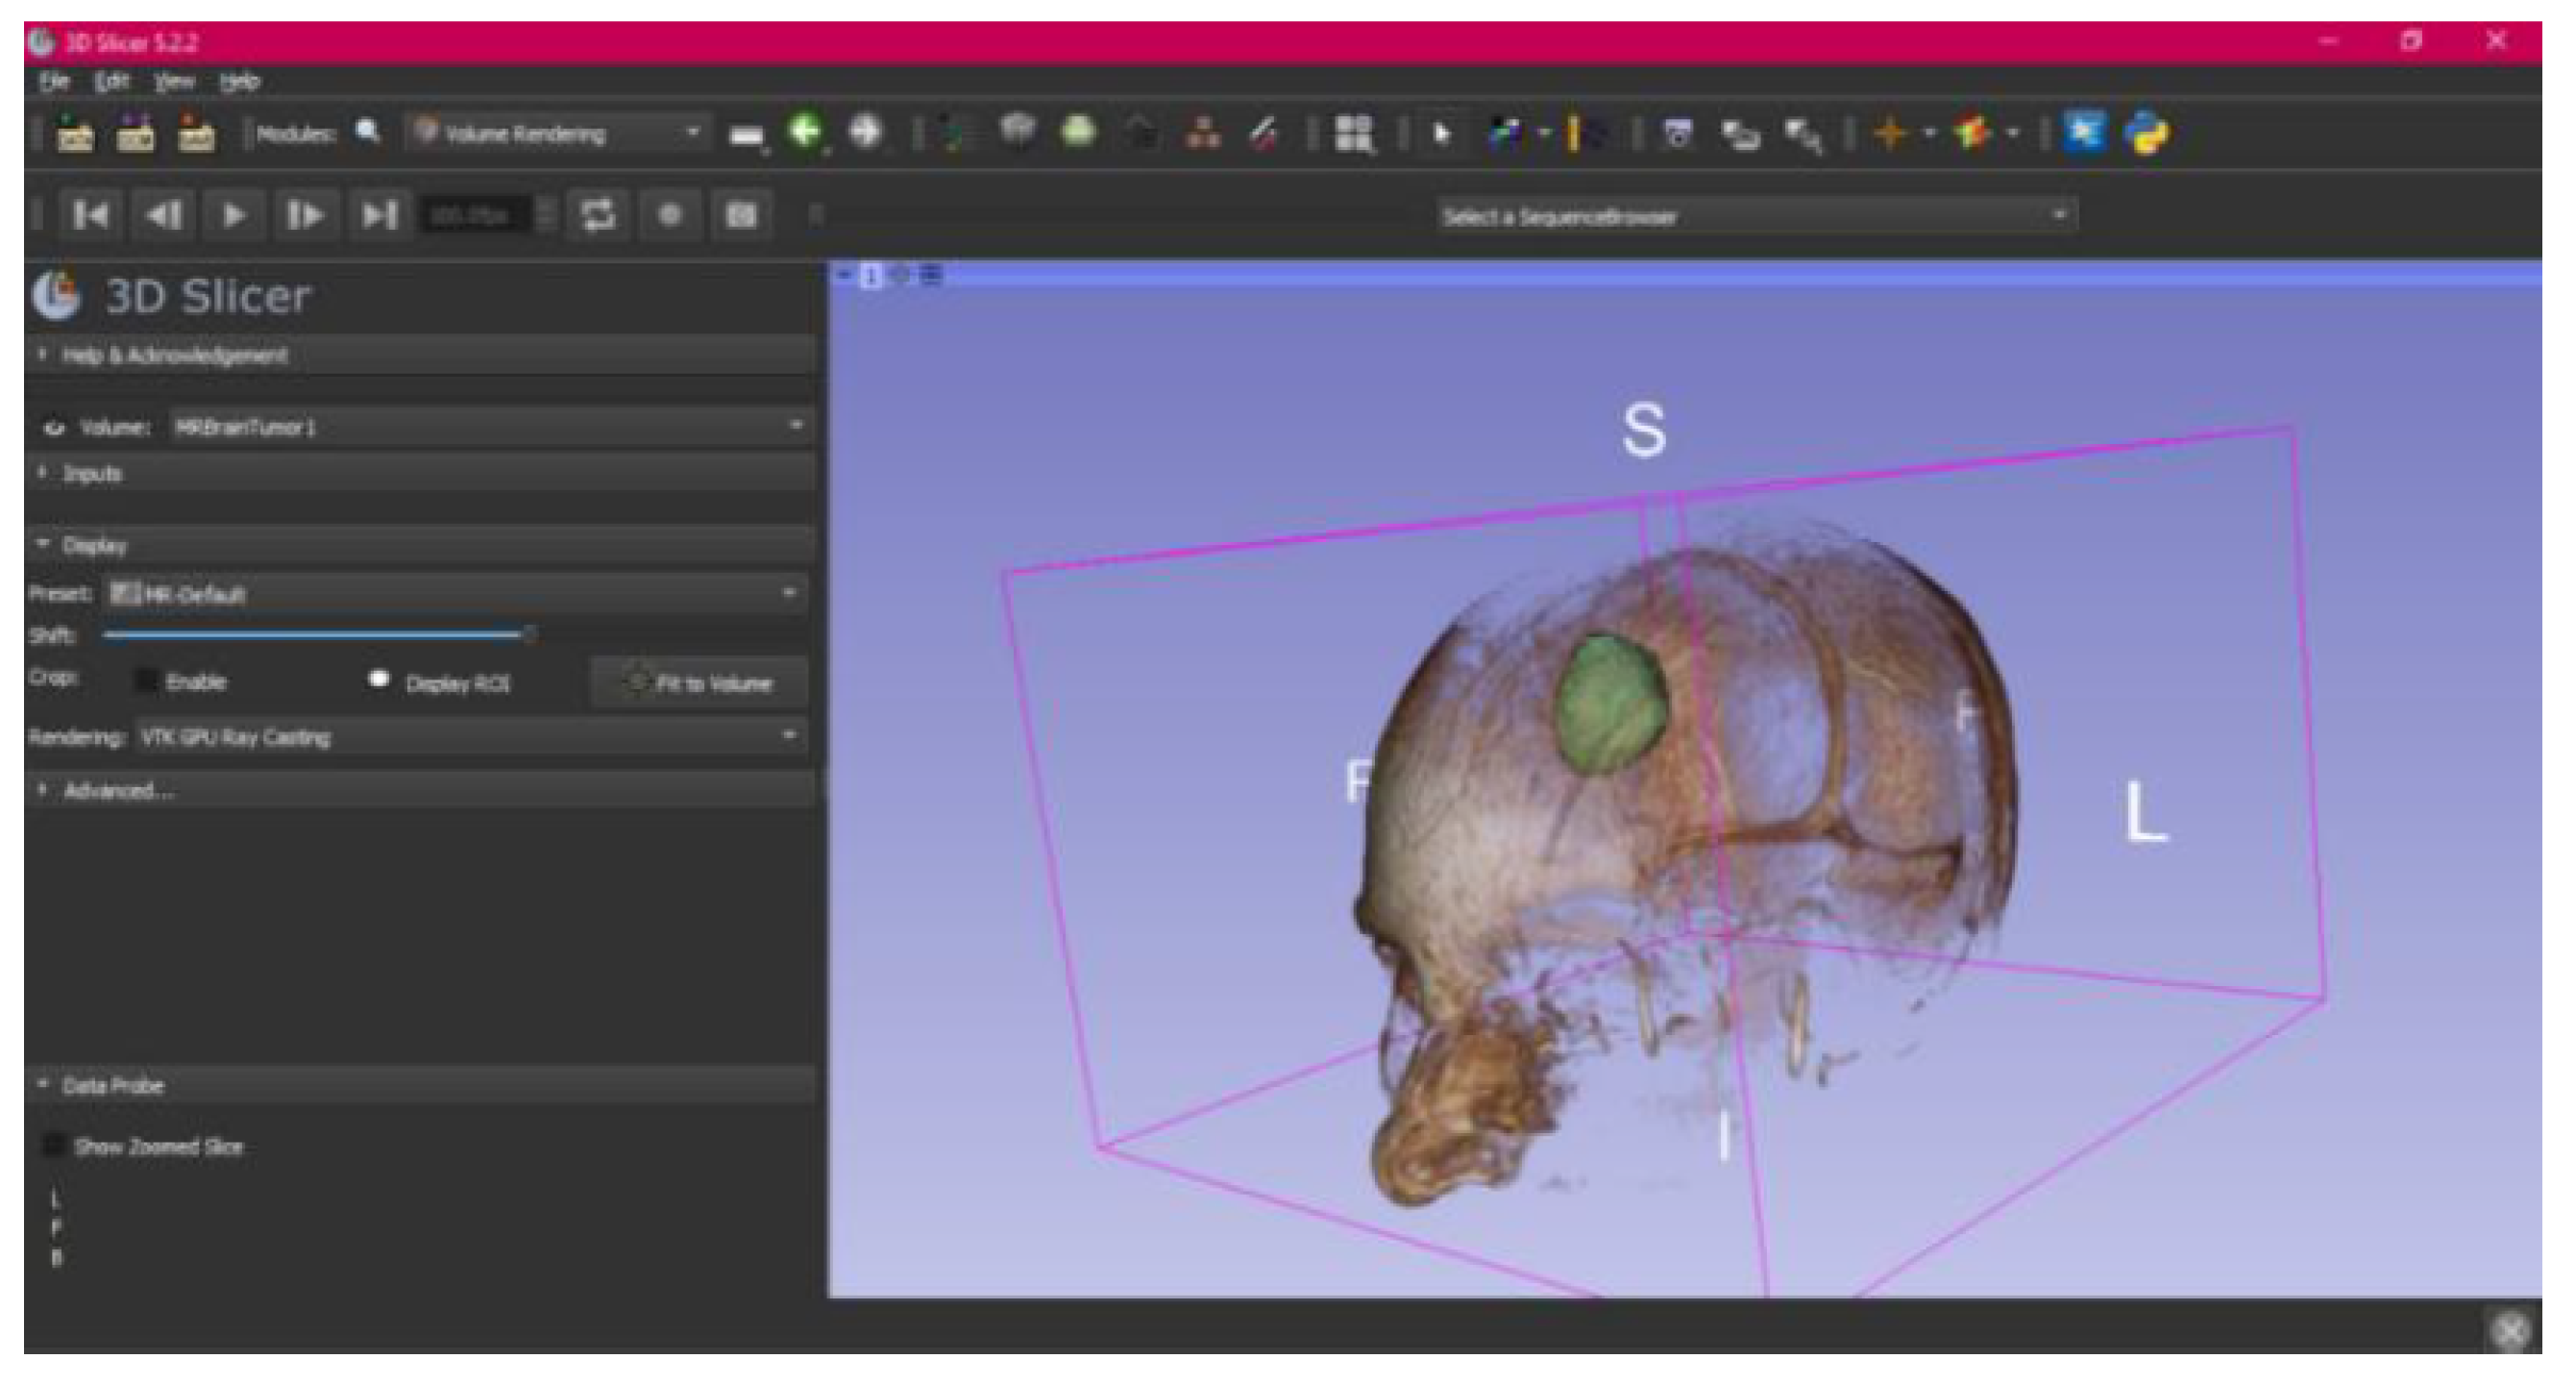

- Select the “Volume Rendering” module in the toolbar.

- Select the volume of interest in the drop-down menu, and activate the rendering function.

- Configure the rendering process by accessing the “Display” drop-down. Choose the most appropriate “preset” option in terms of the image and anatomical model tissue.

- Use the Shift function to adjust the rendered visible tissues, and enable the “Crop” option in order to cut the “region of interest”.

- Make the Region of Interest (ROI) display visible in order to visualise it, and adjust the ROI volume rendering square in the region of interest for the 3D view.

3.3. Human Brain Tumour

3.3.1. DICOM-to-STL Files